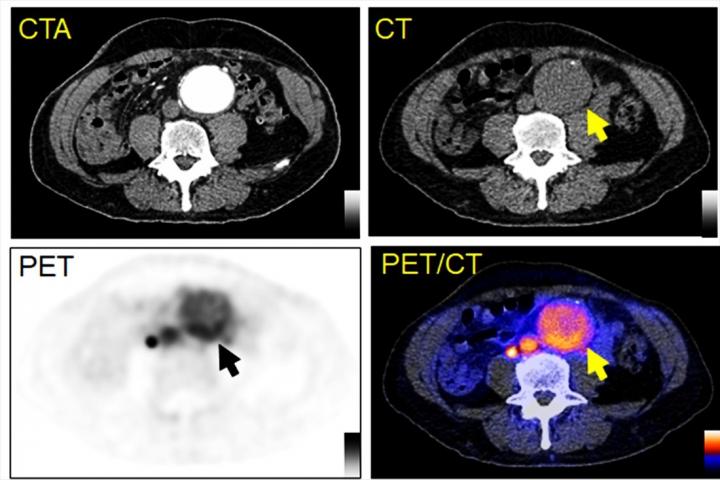

Reston, VA (Embargoed until 6:15 p.m. EDT, Tuesday, June 15, 2021)--A new positron emission tomography (PET) radiotracer can detect abdominal aortic aneurysms (AAAs) and potentially predict when they will rupture, according to research presented at the Society of Nuclear Medicine and Molecular Imaging 2021 Annual Meeting. Targeting a novel biomarker associated with AAA, the radiotracer is effective both in diagnosis and in providing information to assist in the development of AAA treatments, of which there currently are none.

To explore this clinical need, researchers identified chemokine receptor type 2 (CCR2) as a potential, novel biomarker for AAA evaluation. They developed the novel PET tracer, 64Cu-DOTA-ECL1i, and it has been used to perform first-in-AAA patient imaging. 64Cu-DOTA-ECL1i PET was confirmed to be safe and effective for imaging CCR2 in AAA patients.

64Cu-DOTA-ECL1i was also utilized to assess CCR2-targeted treatment in preclinical animal AAA rupture models. In the models, 64Cu-DOTA-ECL1i imaging was highly suggestive of subsequent AAA rupture. Additionally, in a designated cohort of animals that received a CCR2 inhibitor as a form of therapy, researchers were able to demonstrate the effective prevention of AAA rupture.